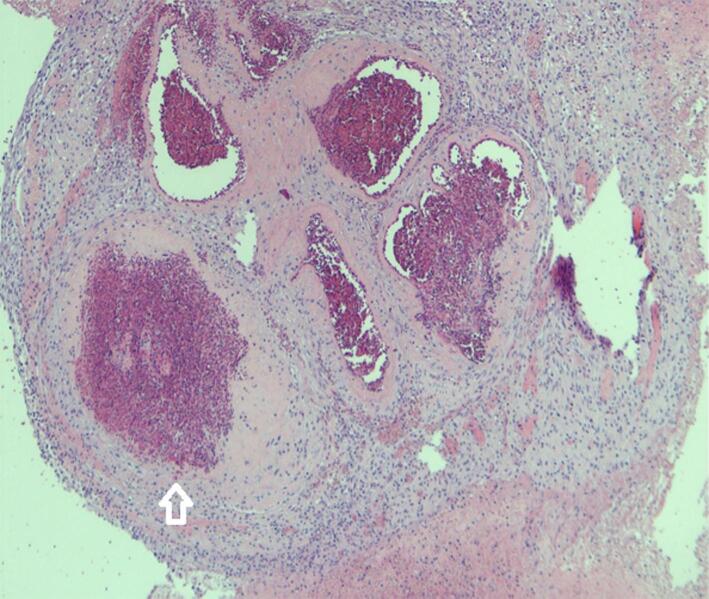

Subinvolution of the placental site can lead to severe post-partum haemorrhage, though it is a rare cause of the condition. Subinvolution of the placental site is an abnormal persistence of widely dilated uteroplacental spiral arteries in the absence of retained products of conception, and is associated with an increased risk of maternal morbidity and mortality. This report presents a case of an uneventful caesarean section that was followed by multiple presentations of major secondary post-partum haemorrhage, with a subsequent diagnosis of subinvolution of the placental site on histopathology. The patient was eventually treated with uterine artery embolisation after trials of medical and other interventional measures.